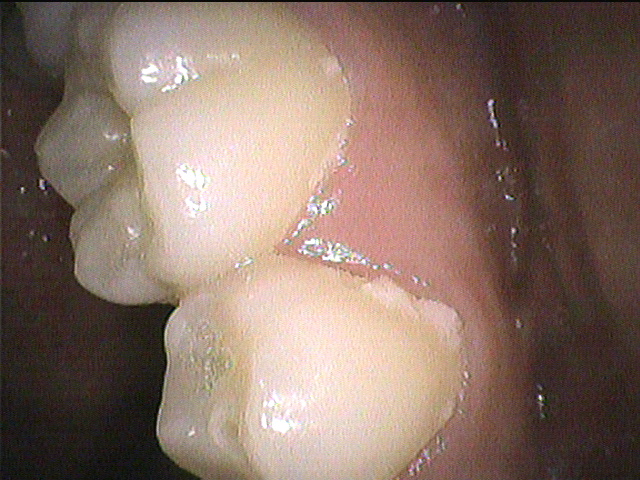

◎クリーニング前 左下の奥歯の表側

◎クリーニング後